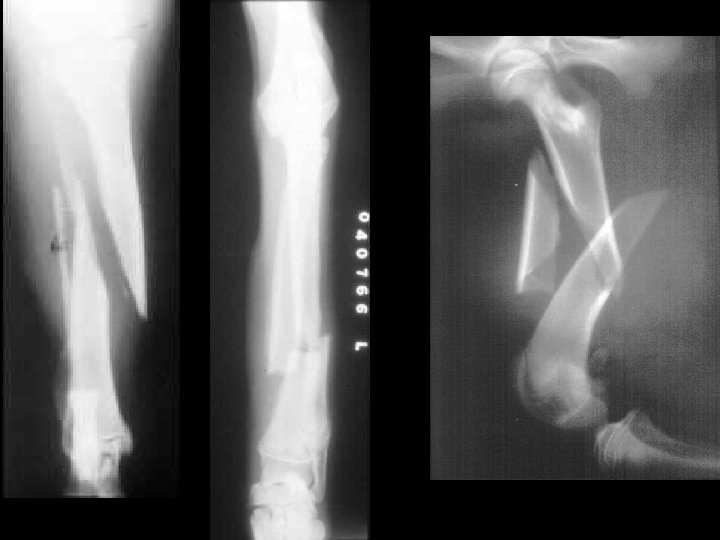

B. Fractures 1. Simple bone breaks cleanly, does not break through skin

B. Fractures 2. Compound broken ends protrude through the skin, risk of bone infection

B. Fractures 3. Greenstick Does not break completely Greenstick: (children)